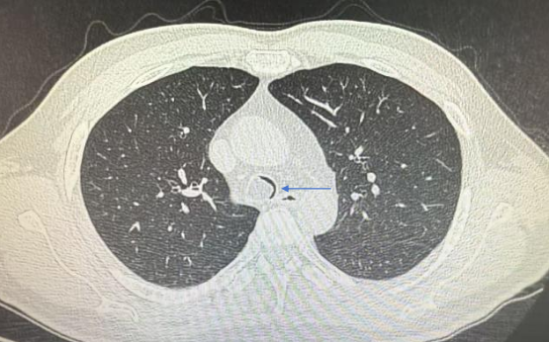

肺部CT示中央气道内新生物堵塞90%

据了解,赵先生因活动后气短就医,自带的肺部CT显示,其中央气道内的异常新生物已堵塞90%气道。中央气道重度狭窄意味着麻醉风险极高,于世寰主任当即牵头组织MDT多学科会诊,与麻醉科刘淑杰主任团队量身定制“精准麻醉+微创介入”方案,为手术保驾护航。